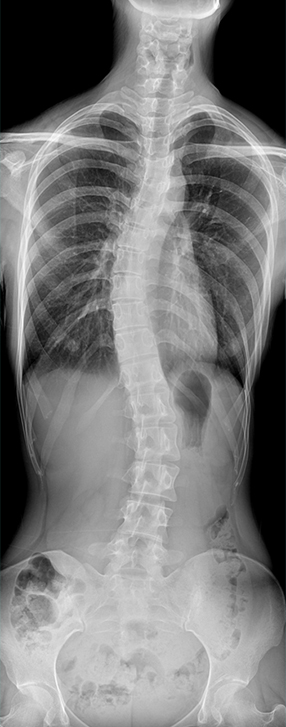

• 拍片

适用于全身各部位摄影

(常规摄影和特殊摄影)

• 标配全身拼接功能

无缝融合处理,保证高质量全景影像。

临床图像